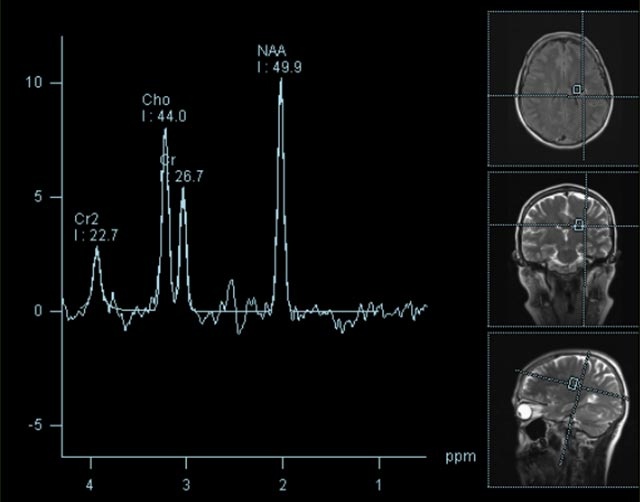

Spezialtechniken der Magnetresonanz

• MR-Spektroskopie

Diese Untersuchung führen wir ausschließlich an unserem Standort in Leipzig am Diakonissenkrankenhaus durch. Bitte nehmen Sie zur Vereinbarung eines Termins telefonischen Kontakt mit uns auf: 0341 3937-3000 oder schreiben Sie uns eine E-Mail an: